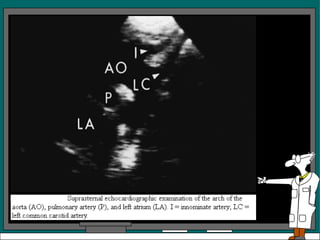

Vista Supraesternal Es una vista paralela o perpendicular al arco de la aorta En la vista paralela se ve la aorta, la arteria pulmonar y la auricula izquierda, con la tecnica de barrido se podria visualizar tambien la arteria innominada, la carotida izquierda y la subclavia izquierda

Un examen supraesternal en el eje corto del arco de la aorta, revela una aorta circular, la arteria pulmonar y parte de la auricula izquierda, se observa tambien la bifurcacion de la arteria pulmonar.